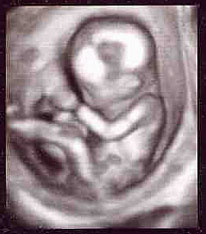

さてさて、早速お腹をエコーでチェックしてみると、

赤ちゃんがすっかり人間らしくなっていました!

手足が長くなり、指も1本1本きれいに伸びて、

お腹の中で元気に動き回っていましたよーー!

そして、いつもの3D画像だけでなく、4Dも見せてくれたのですが、

あまりの鮮明さに画面を覗きながらぎょっとしてしまいました。

(だから、文章の最後に載せておきます。)

それではお待ちかねの4D画像です。

16W5D(16週と5日)

身長(頭のてっぺんからお尻まで):10.28cm